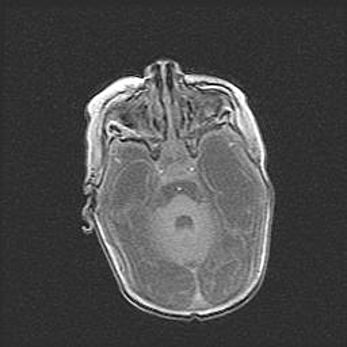

Подострая гематома правой гемисферы мозжечка.

Наружная гидроцефалия.

Возраст: 15 дней

Вес: 3100 г

Пол: женский

Окружность головы: 37 см

Срок гестации: 35-36 недель

При открытой наружной форме гидроцефалии у новорожденных расширяются и переполняются субарахноидные пространства.

Кровоизлияния в мозжечок имеют две клинико-анатомические формы: полушарные гематомы и кровоизлияния в червь.

К появлению этой патологии может привести: повреждения головного мозга, возникающие в результате асфиксии и гипоксии плода при беременности, или травмы во время родов. Редко гематома мозжечка может быть результатом первичной коагулопатии и сосудистой мальформации, диссеминированном внутрисосудистом свертывании, изоиммунной тромбоцитопении.